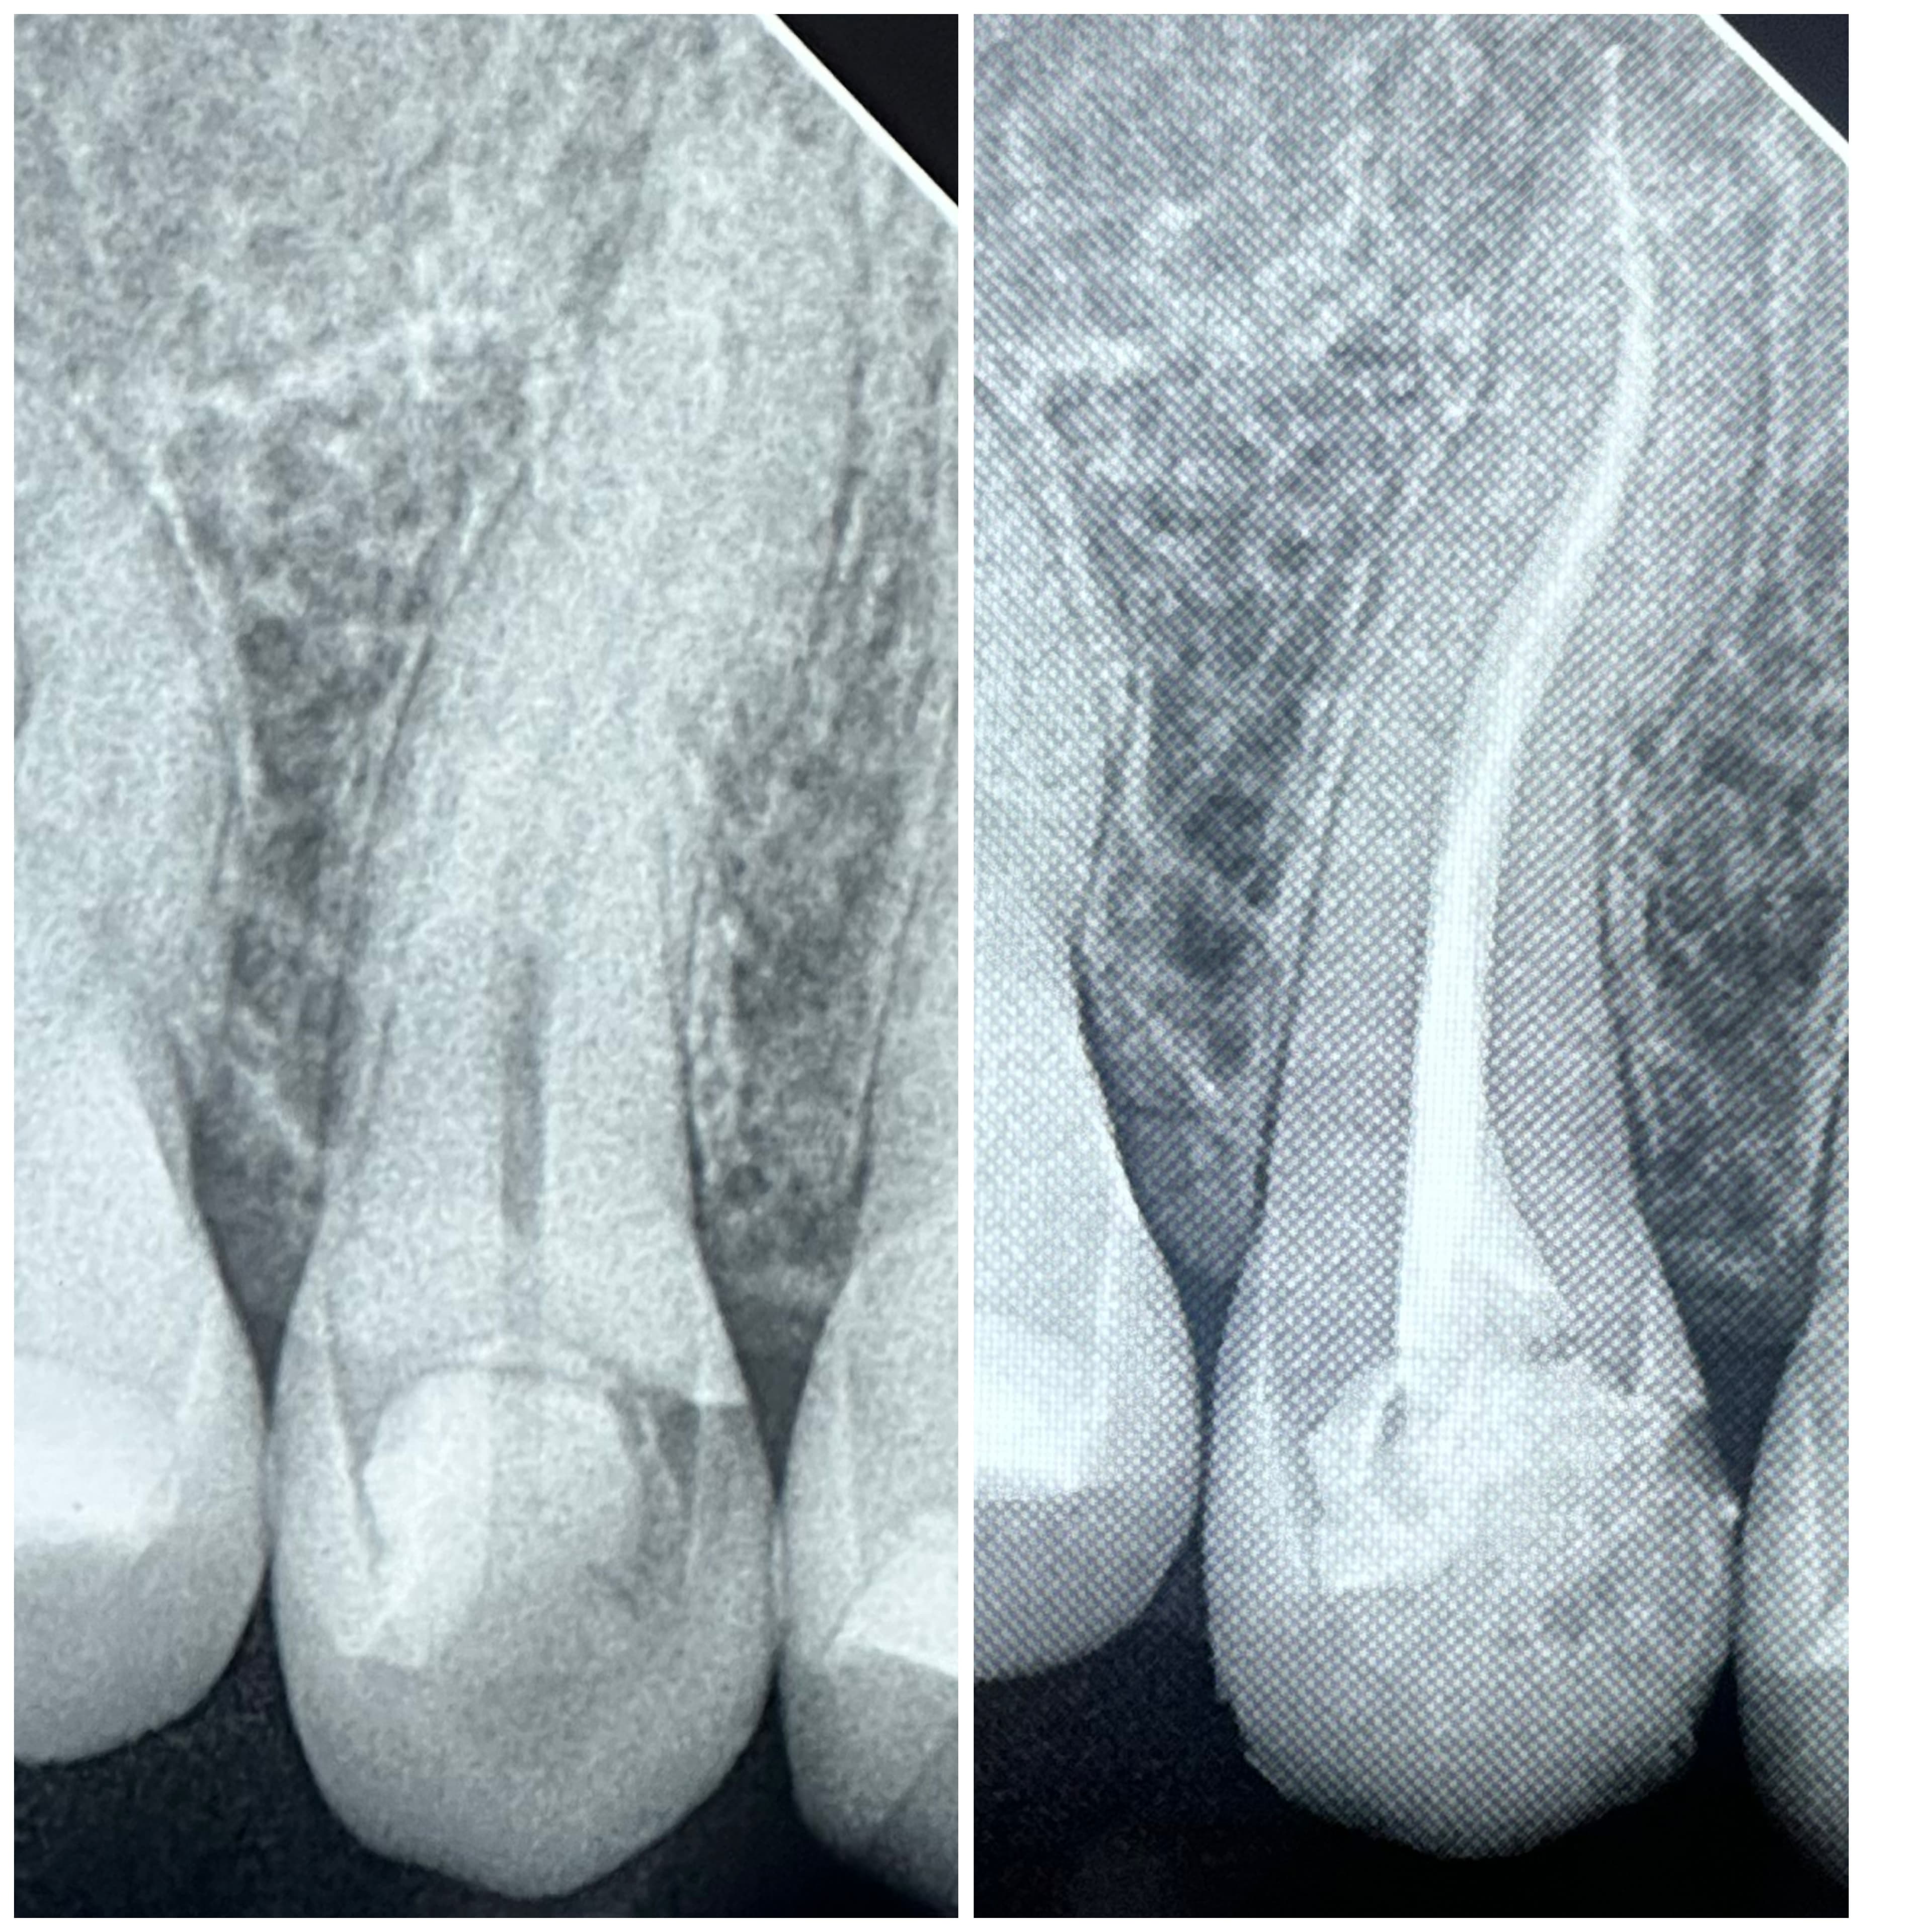

Nuestros Trabajos